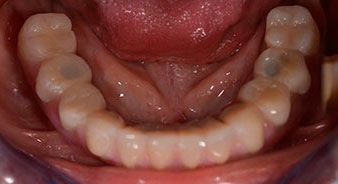

The 64-year-old patient presented with residual dentition of teeth 38, 33 and 43 and a clasp denture in the mandible (Fig. 1 and 2).

residual dentition

Fig. 1